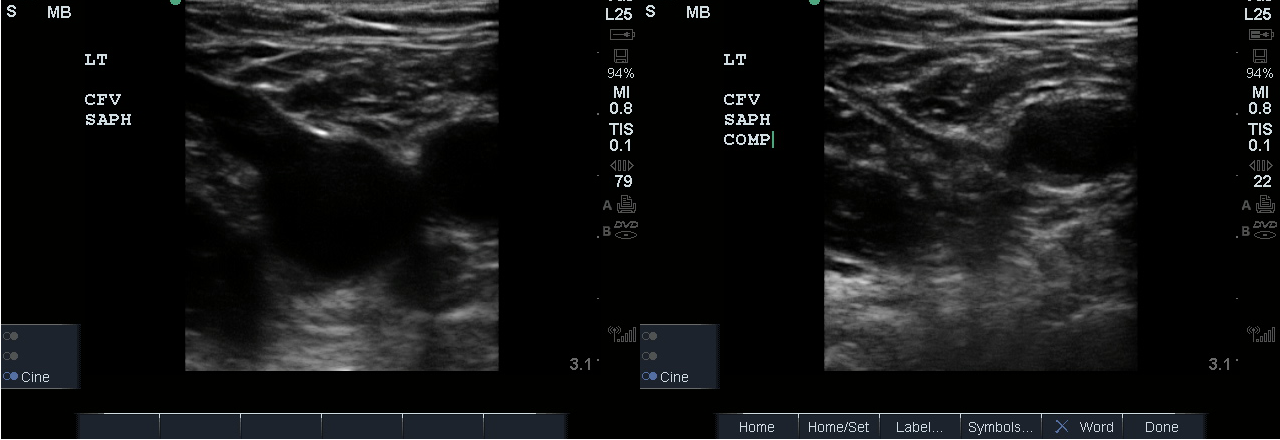

- Identify the inguinal crease at the very proximal medial thigh and place the transducer in a transverse orientation as indicated in Fig. 8. You should see the CFA and CFV as in the corresponding ultrasound image. If you see three vessels (CFA, CFV, SV), you are not proximal enough. Compress the CFV (Fig. 8 and 9).

- Slide the transducer distally 1 to 2 cm to the junction of the CFV and GSV ( 10 and 11) and compress.

- Figure 11. Compression of the CFV at the junction of the GSV 1-2 cm below the inguinal crease.

- Slide the transducer another 1 to 2 cm (3-4 cm distal to the inguinal ligament) to the junction of the DFV and FV. You will also see the CFA branch into the FA and DFA (Fig. 12). This constitutes completion of evaluation of “region 1.”